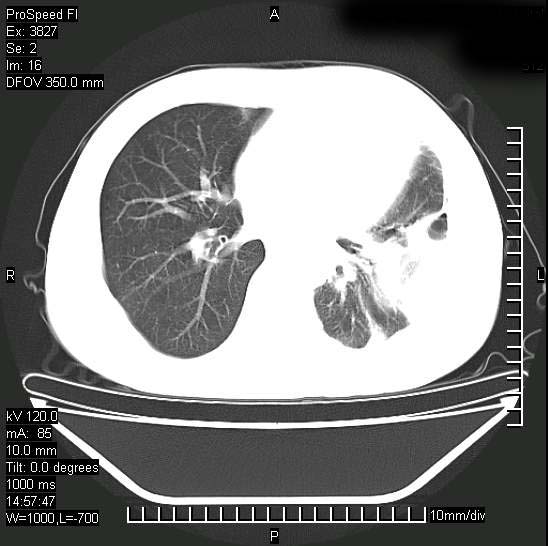

男性,一月前出现右侧肋区疼痛,较剧烈,干咳,无发热,自诉使用抗炎药后缓解,几天前又出现左侧剧烈疼痛,

发热,体温38。9,今天ct,考虑左侧包裹性脓胸,胸腔积液,右上中肺小斑片影,结核/炎症?胸水未见恶性细胞。